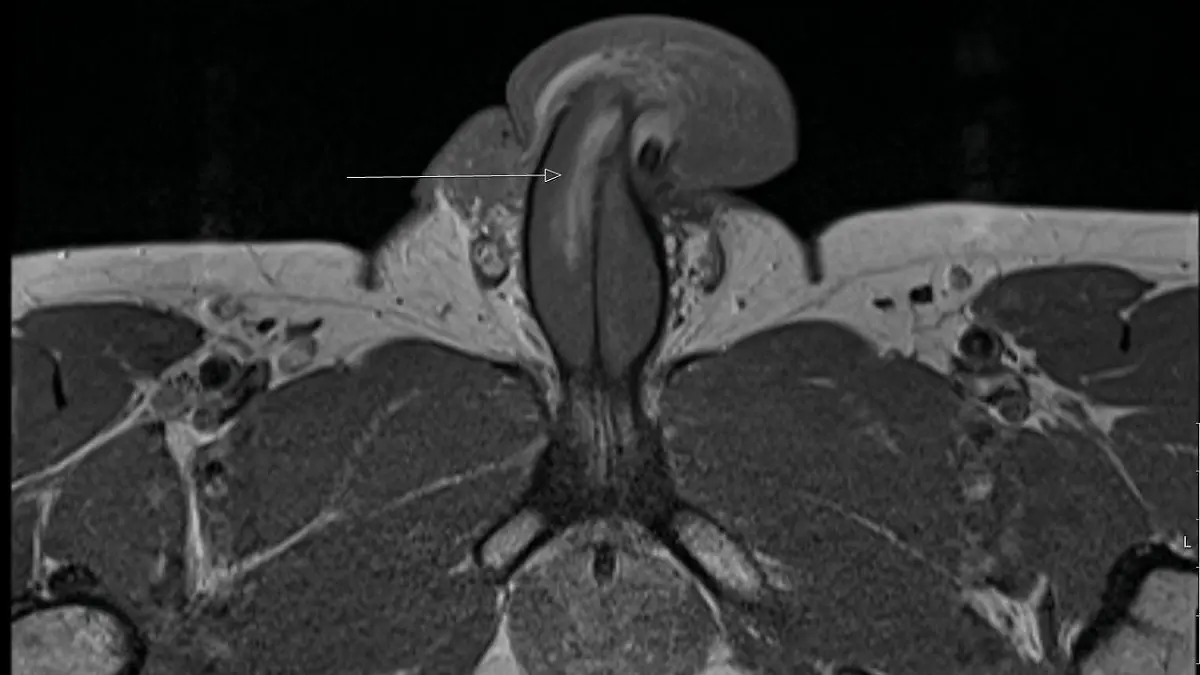

Dem Bericht zufolge wurde dann im Krankenhaus ein MRT durchgeführt und dabei stellte sich heraus, dass der Patient einen vertikalen Riss in der Bindegewebshülle am rechten Schwellkörper entlang eines Drittels seines Penisses erlitten hatte.